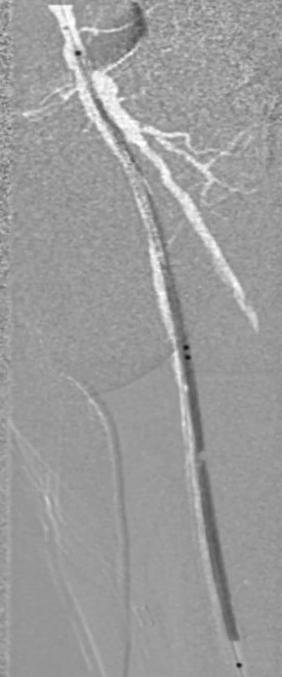

穿刺与造影定位

穿刺右侧股总动脉,置入8F翻山鞘,行左下肢动脉造影,可见左股浅动脉长段闭塞,远端流出道尚通畅。

既往支架已遮盖股浅动脉起始段